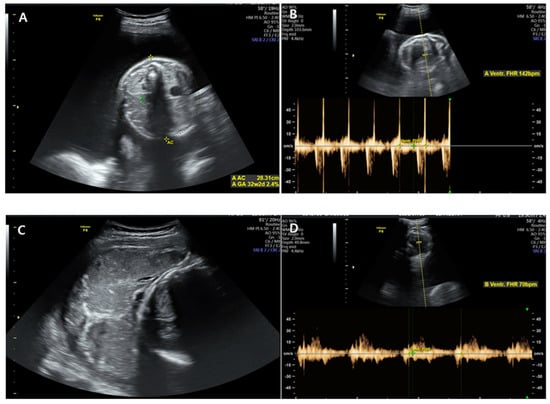

Figure 2. Ultrasonography was performed at admission. (A,B) showed the first fetus located on the left side of the mother. The fetal heart rate was 140–160 beats/min with good fetal motion, and amniotic fluid volume index (AFI) was more than 30 cm, showing polyhydramnios. (C,D) showed the second fetus located on the right side of the mother with breech presentation. The heart rate was 70–80 beats/min, showing a consistent bradycardia.

Initially, the patient’s vital signs were stable and as follows: blood pressure, 125/75 mmHg; pulse rate, 98 beats/min; respiratory rate, 20 breaths/min; body temperature, 36.6 °C; and oxygen saturation, 99%. Cervical examination revealed 10% cervical dilatation, 50% effacement, and −2 fetal station. Ultrasonography showed that the first fetus was located on the left side of the mother in a vertex presentation and that the fetal heart rate was 150–160 beats/min with good fetal motion, but the amniotic fluid volume index (AFI) was more than 30 cm, showing polyhydramnios. The second fetus was located on the right side of the mother and exhibited a heart rate of 70–80 beats/min and consistent bradycardia with a breech presentation, showing oligohydramnios (Figure 2). No evidence of placental abruption was noted. Continuous fetal monitoring was performed while preparing for an emergency cesarean section, and continuous fetal bradycardia of the second fetus was noted as 30–40 mmHg of uterine contractions at 5–6-min intervals.